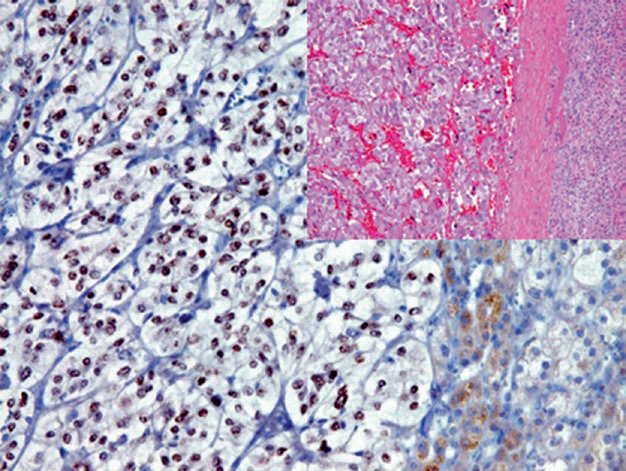

图片

图2. 肾上腺皮质腺瘤,inhibin在胞质阳性。

图3. 嗜铬细胞瘤,免疫组化CD56(左)、Syn(右)均为强阳性表达。